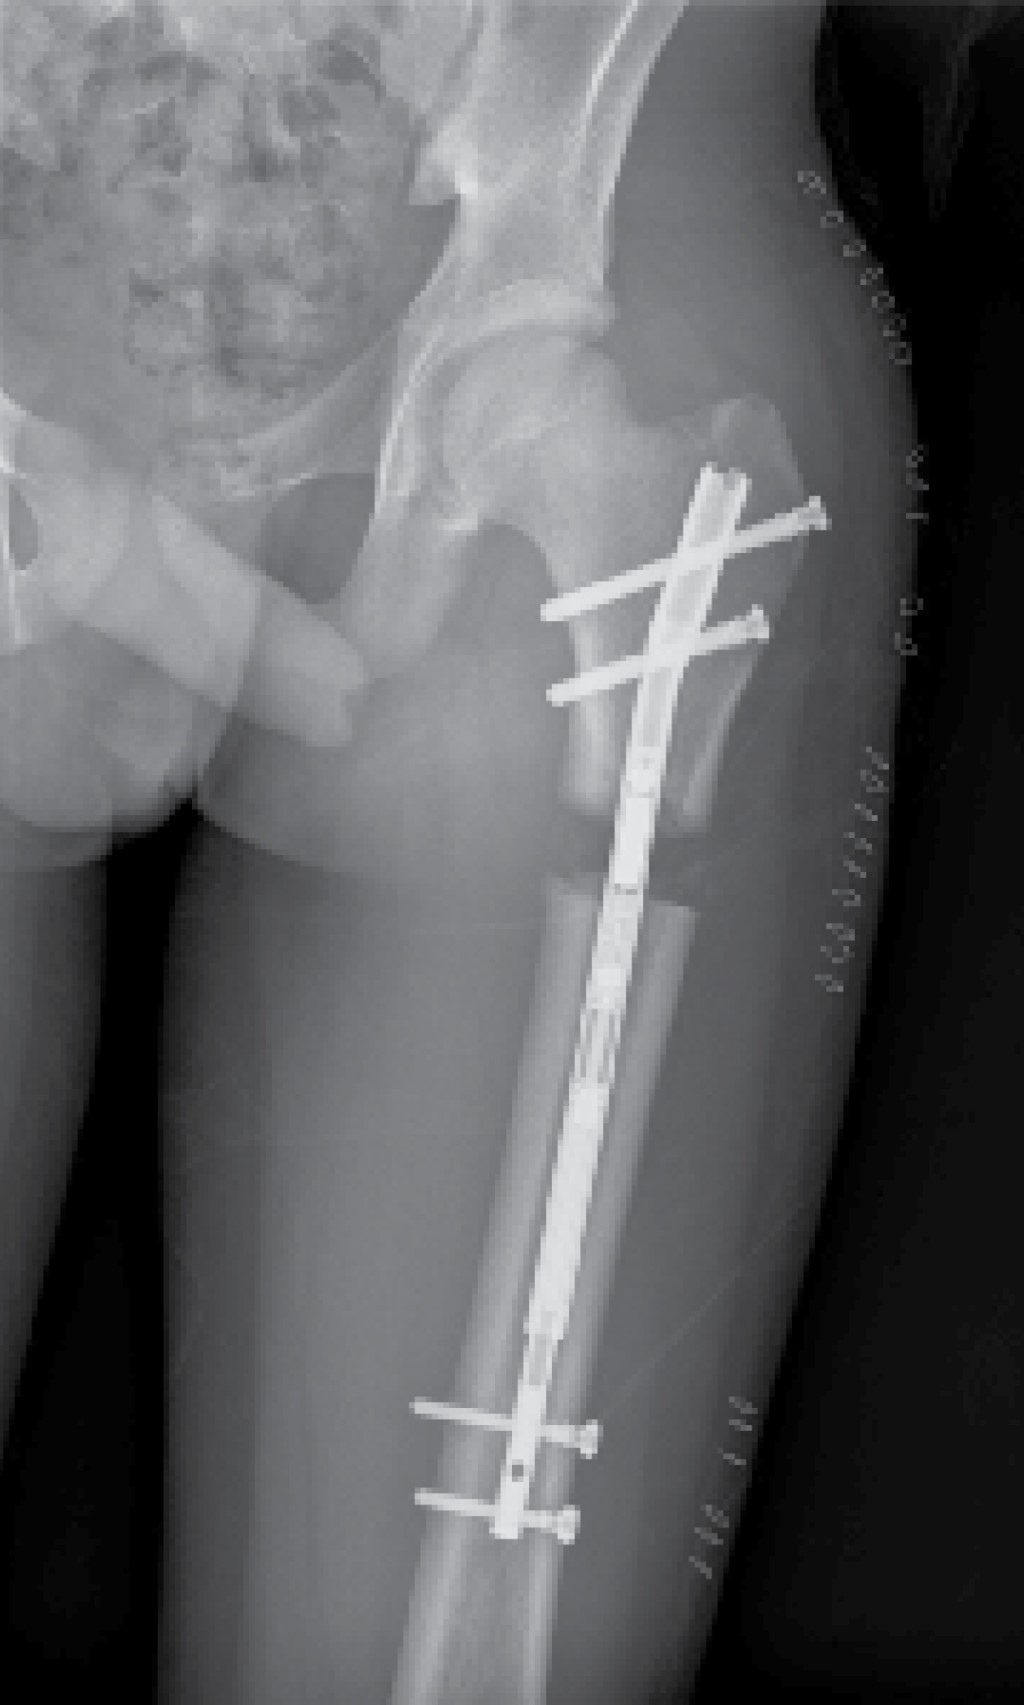

Se identificó el lugar de la osteotomía femoral siguiendo el método habitual descrito por Paley y colaboradores,13 realizándose mediante múltiples perforaciones a través de un abordaje lateral. Como describen algunos autores, estas perforaciones registran una baja tasa de tromboembolismo pulmonar.2 El punto de entrada del clavo se realizó en la punta del trocánter mayor a través de un abordaje lateral proximal (Figura 1), que permitió el fresado del canal femoral hasta 1.5-2 mm mayor que el diámetro definitivo del clavo seleccionado. Se introdujo el clavo intramedular Precice® hasta el borde proximal de la zona de osteotomía y se completó la misma a través del abordaje lateral, introduciendo el clavo hasta su localización definitiva y bloqueándolo proximal y distalmente (Figura 2). Por último, se realizó la distracción del clavo 1-2 mm para asegurar el correcto funcionamiento del dispositivo magnético.

Todos los pacientes fueron instruidos para el correcto funcionamiento del dispositivo y comenzaron el alargamiento femoral a la semana de la intervención en torno a 1 mm/día. El primer control radiográfico se realizó a los siete-10 días de la intervención y posteriormente, de manera sucesiva, cada dos semanas hasta el final del alargamiento (Figura 3), cuantificando el mismo en cada revisión. Después se realizó un seguimiento mensual durante la fase de consolidación (Figura 4), la cual comprende desde el final del alargamiento femoral hasta la consolidación ósea de la zona alargada (Figura 5). Por último, se realizaron controles a los seis meses, al año y a los dos años de la cirugía.

De los cinco clavos utilizados, tres tenían un diámetro de 10.7 mm; uno, un diámetro de 8.5 mm; y otro, de 12.8 mm. Tres clavos tenían una longitud de 215 mm; uno, de 230 mm; y otro, de 245 mm. Todos los clavos fueron femorales y anterógrados.

Figura 2